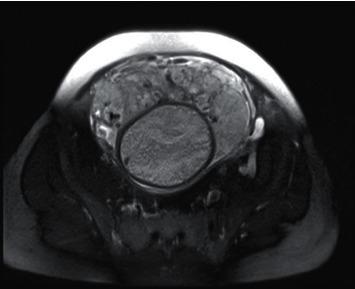

To explore the value of magnetic resonance imaging (MRI) in measuring the volume of T2 low-signal band and the width change of the widest blood vessel in placenta in pregnant women with different types of placenta implantation (PI).

From November 2020 to August 2021, 116 patients in our hospital who underwent placental MRI because of ultrasound or clinical suspicion of PI were selected as the research object. According to the "gold standard" (clinical or surgical pathological results), 79 cases with PI were diagnosed as PI group, and 37 cases without PI were no PI group. The clinical features, MRI signs, T2 hyposignal zone volume, and the width of the widest blood vessel in placenta were compared between the two groups and different types of PI patients. Logistic regression was used to analyze the influencing factors of PI and PI classification, and the receiver-operating characteristic (ROC) was used to analyze the value of T2 low-signal zone volume and the widest blood vessel width in the placenta for different types of PI.

The history of cesarean section, uneven placental signal, the proportion of T2 low-signal band shadow, the volume of T2 low-signal band, and the width of the widest blood vessel in placenta in PI group were higher than those in non-PI group ( < 0.05); the history of cesarean section, uneven placental signal, T2 hypointense band shadow, the volume of T2 hypointense band, and the increase of the width of the widest blood vessel in placenta are independent risk factors for PI ( < 0.05); with the increase of implantation depth, the proportion of T2 hypointense band shadow, the volume of T2 hypointense band, and the width of the widest blood vessel in placenta gradually increased ( < 0.05); T2 hypointense band shadow, T2 hypointense band volume, and the widest blood vessel width in placenta are all influencing factors of PI classification ( < 0.05); ROC showed that the volume of T2 low-signal band and the width of the widest blood vessel in placenta, the AUC of combined identification of adhesive PI, implanted PI, implanted PI, and penetrating PI were 0.846 and 0.899, respectively, which was higher than that of single identification ( < 0.05).

MRI measurement of T2 hyposignal zone volume and the widest blood vessel width in placenta can be used for PI diagnosis and classification differentiation and provide reliable basis for clinical prenatal preparation and treatment planning.